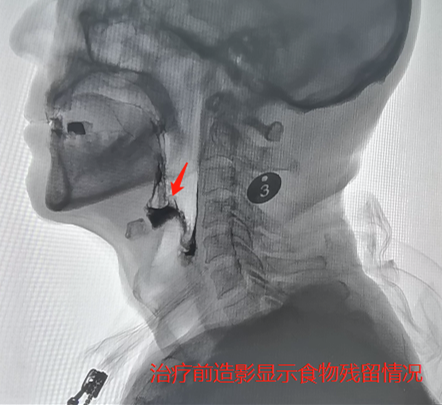

91岁的尤爷爷身体还算硬朗,可最近老人总是食欲差、乏力,还时不时地发烧,家人觉得很蹊跷,老人最近并没有受寒,应该不是着凉感冒,遂将尤爷爷送到捷克论坛 。经检查,尤爷爷咽部有大量食物残留,因吞咽障碍导致隐性误吸引发了肺炎。

尤爷爷被收入康复医学科二病区,经过口颜面感觉运动训练、气道保护训练、体位调整、姿势代偿、食物调配等个体化治疗后,他的咽部食物残留、误吸情况得到明显改善,营养状况持续好转,肺部感染也得到了有效控制,今日顺利出院。